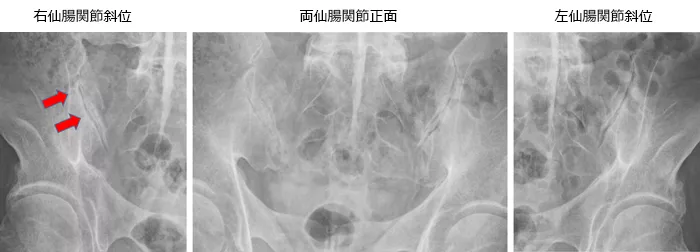

写真1

椎体間の靭帯骨棘あり(赤矢印)。

椎間関節は骨性癒合あり(青矢印)。